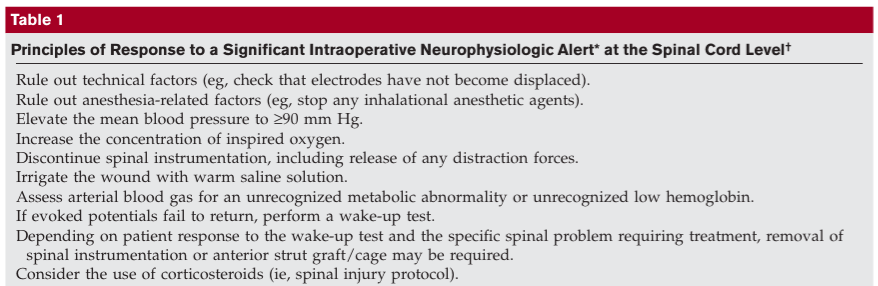

6 things to do if a neuro alert during scoliosis surgery

- check equipment

- check blood pressure >90mmHg

- check Hgb

- reverse or lessen correction

- wake up test

- remove implants if spine stable